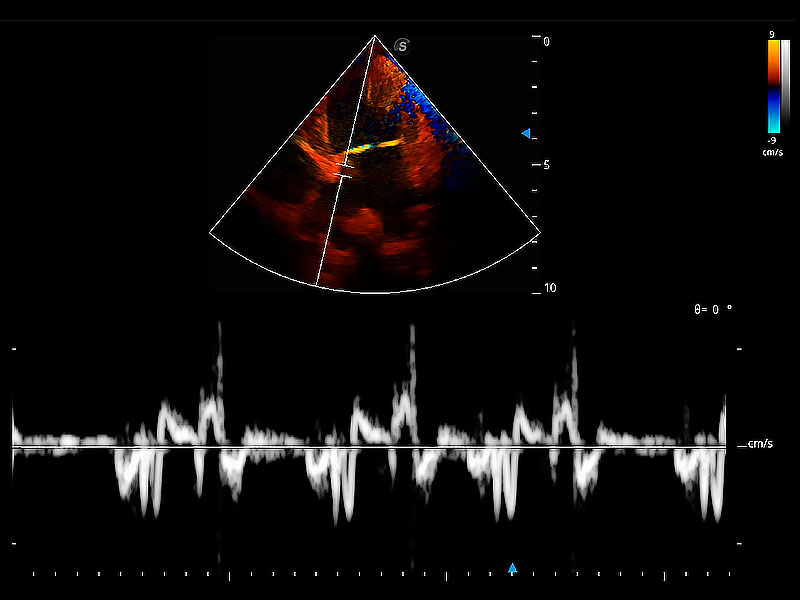

實時用顏色表示心肌組織運動,觀察和定量組織的運動情況,對快速檢測與評估心肌的灌注和活性、電傳導及心肌收縮和舒張功能等均能提供重要的診斷信息。

通過360度任意調(diào)節(jié)3條M型取樣線,在同一心動周期上觀察心臟不同位置的運動曲線,得到準確的心功能測量數(shù)據(jù),有效評估心肌運動及左心室功能。